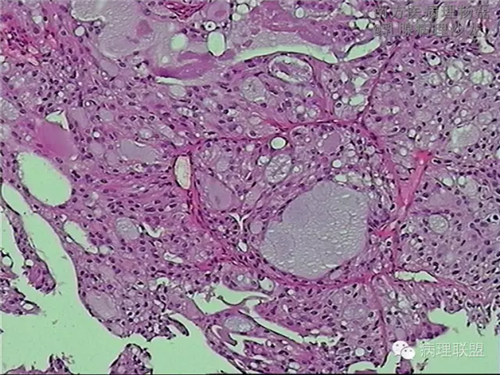

肺转移性乳腺分泌性癌?-病例讨论

女,51,右肺多发结节穿刺。15年前行右乳肿物切除,具体不详。